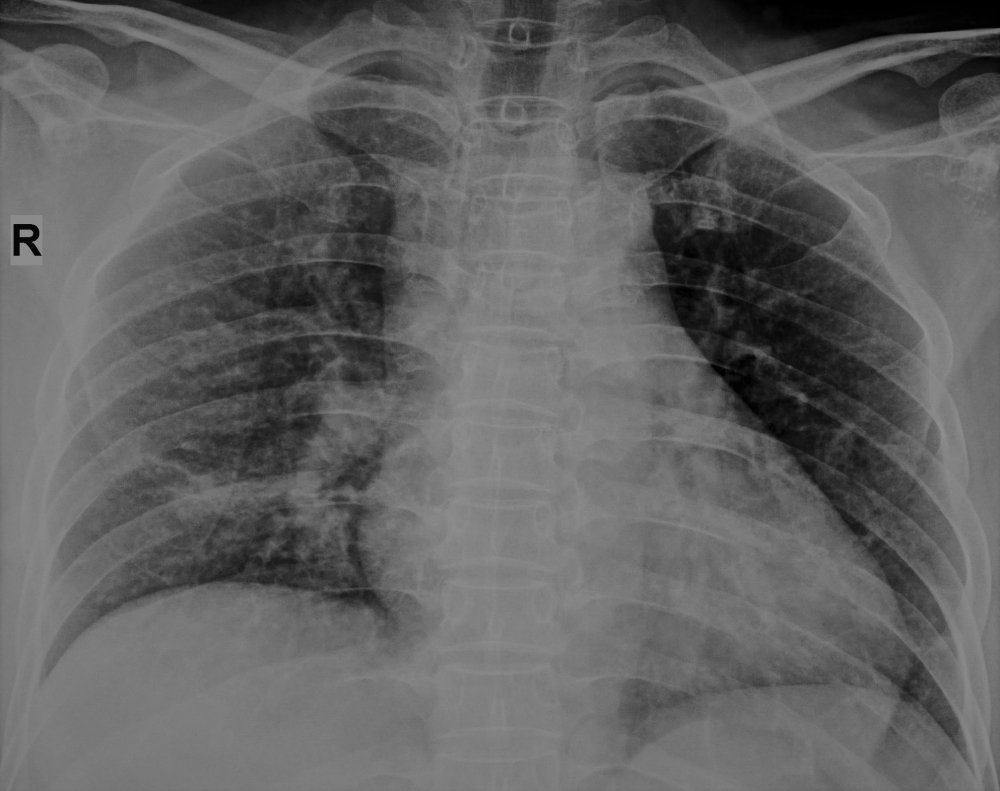

Tại đây, các bác sỹ đã hội chẩn với sự hỗ trợ từ IBM Watson for Oncology. Phác đồ điều trị do hệ thống Trí tuệ nhân tạo Watson đưa ra có sự thống nhất cao với hội đồng chuyên môn. Chị H. được quyết định điều trị với một thuốc điều trị trúng đích sinh học thế hệ 3 mới nhất, cùng chỉ định xạ trị giảm triệu chứng vào vị trí di căn xương. Và thật kỳ diệu, sau 1 tháng điều trị, chị H. hoàn toàn có thể đi lại bình thường, không phải sử dụng thuốc giảm đau, và phim chụp phổi của chị đạt được sự đáp ứng rất tốt, các khối u đã gần như biến mất.

Phổi trước khi được điều trị

Phổi sau khi điều trị